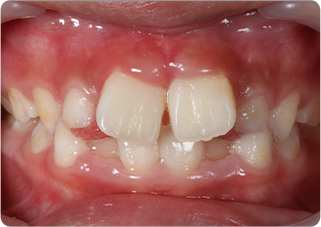

上唇小帯切除症例

術前

術後

| 主訴 | 上の前歯のすきっ歯が気になる |

|---|---|

| 治療期間/回数 | 1ヵ月、3回 |

| 価格(税込) | 保険適応 |

| リスク・副作用 | 出血、術後疼痛の可能性 |

| ポイント | 上唇小帯の付着異常により、正中離開が起きていた。上唇小帯を電気メスで切除した結果、歯を正中に寄せることが出来た。 |